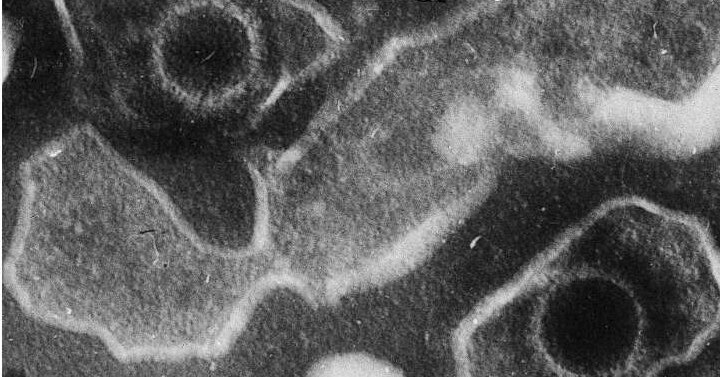

Вирус Эпштейна-Барра

Вирус Эпштейна-Барра есть у 95% людей, даже если они об этом не знают. Им заражаются преимущественно через слюну. В детстве — когда дети делятся ложкой или пьют из одной чашки. Или позже, в подростковом возрасте, через поцелуй.

ВЭБ — частая причина инфекционного мононуклеоза, которая проявляется высокой температурой и изнурительной усталостью, длящейся месяцами. Особенность вируса в том, что он никогда не покидает организм. ВЭБ как и вирус ветрянки, герпеса просто находит себе укрытие внутри клеток и переходит в спящий режим.